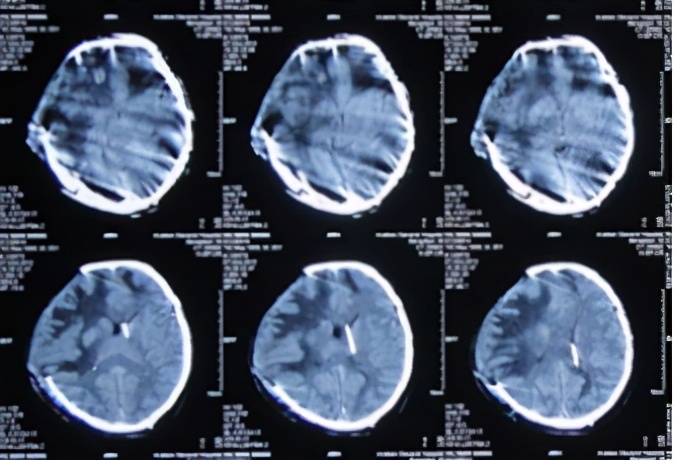

2014年3月24日即留置硬膜外积液持续引流第14天即颅骨修补术后第27天(开颅术后第190天),复查头CT:硬膜外积液及中线移位均再次减轻(图-28)。并在此次复查CT后拔除硬膜外引流管,继续给予静脉抗感染治疗。

图-28:2014年3月24日头CT

此后又分别于2014年3月31日(图-29)、2014年4月8日(图-30)、2014年5月5日(图-31)复查头CT显示硬膜外积液逐渐吸收并基本消失。且此期间患者状态也明显改善,已可以下床活动(图-32)。

图-29:2014年3月31日头CT

图-30:2014年4月8日头CT

图-31:2014年5月5日头CT